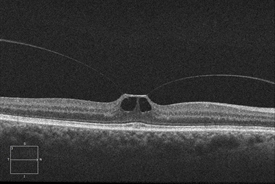

Optical coherence tomography (OCT) is a commonly used and recommended method to noninvasively identify and monitor VMT syndrome. This technology captures cross-sectional images of the retinal layers, including the surface, and allows physicians to evaluate the degree to which vitreomacular tractional forces are distorting the retinal structure.